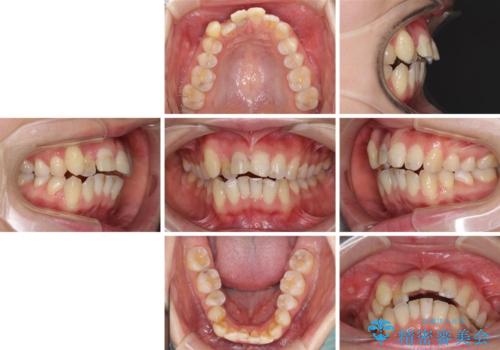

- 転倒により前歯の一部が欠けてしまったとのことで来院された患者様です。

神経が保存できる歯、神経を除去しなければならない歯、抜歯が必要な歯があり、ブリッジやインプラントなどによる治療を提案しました。

元々歯並びが気になっていたとのことで、前歯の治療を行うことを契機に矯正治療も行うこととしました。

本来であれば積極的に小臼歯を抜歯して口元を下げても良いのですが、前歯を1本抜歯しないといけなくなったため、非抜歯矯正をインビザラインを用いて行うこととしました。